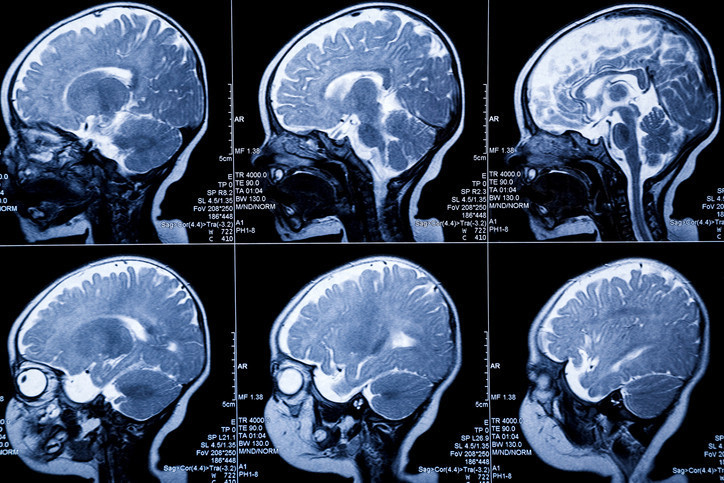

Araştırmanın yazarlarından Zhejiang Üniversitesi Tıp Fakültesi Öğretim Üyesi Profesör Changzheng Yuan, MIND diyetine daha sıkı bağlı kalan bireylerin 12 yıllık takip süresi boyunca yapısal beyin yaşlanmasının daha yavaş seyrettiğini ifade ediyor.

Özellikle hafıza, düşünme ve karar verme süreçlerinde görev alan sinir hücrelerini barındıran gri maddenin korunması, bu diyetin en belirgin sonuçlarından biri olarak öne çıkıyor.

Çalışma verilerine göre, diyete uyum puanındaki her üç puanlık artış, gri maddedeki küçülmenin yüzde 20 oranında azalmasını sağlıyor. Bu oran, beyin yaşlanmasında yaklaşık 2,5 yıllık bir gecikmeye tekabül ediyor.

Hem Akdeniz hem de MIND diyetlerinin bilişsel gerilemeyi yavaşlattığı ve Alzheimer riskini düşürdüğü geçmiş çalışmalarda da belirtilmiş olsa da bu yeni bulgular, söz konusu beslenme tarzının fiziksel beyin yapısını nasıl koruduğuna dair somut kanıtlar ekliyor.